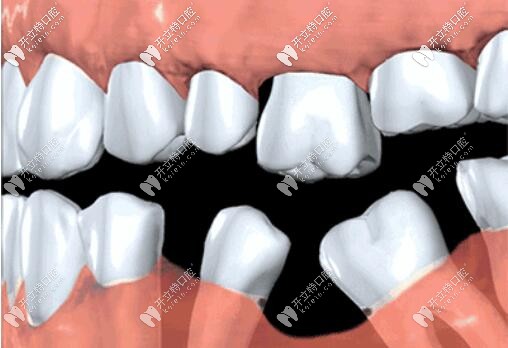

很多人覺得缺一兩顆牙沒事,殊不知,長期咬合不平衡,導(dǎo)致缺牙部位鄰牙傾倒,對頜牙伸長,整口牙不整齊,都會影響口腔健康牙齒,加快其他牙脫落。

而且牙齒缺失牙槽骨很快萎縮,再想種牙,有可能骨量不夠,需要植骨,增加額外費用,所以缺牙一定要及時鑲牙,不單是為了健康,也為了幫你省錢。